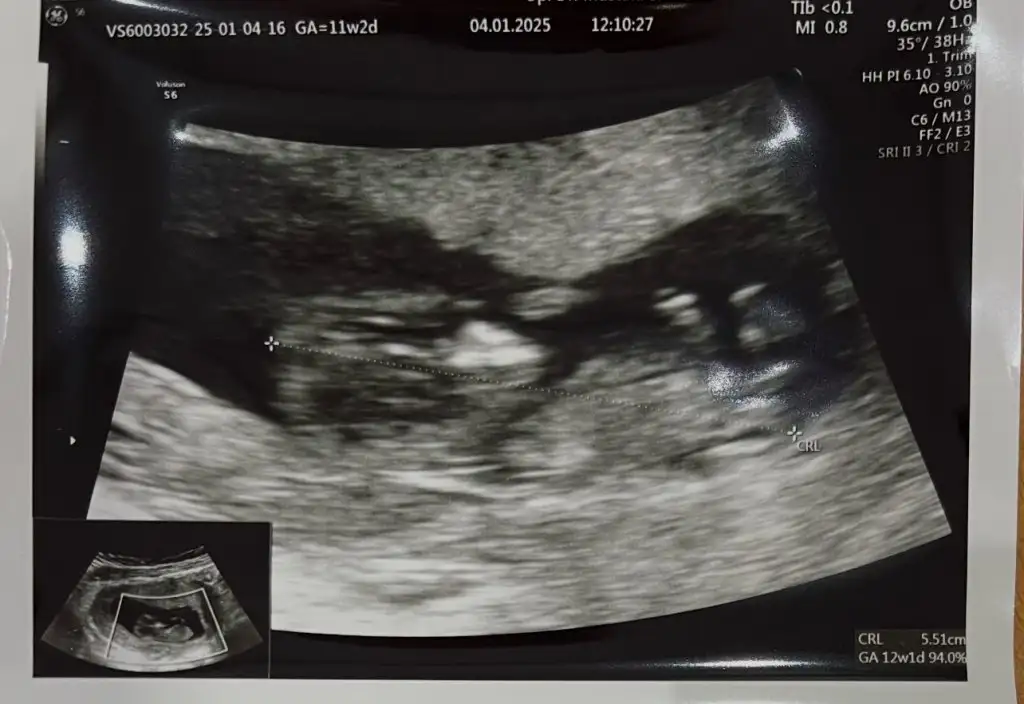

Buda 12+2 haftalık hala aynı fikirde misiniz acaba?Sizinki de erkek gibi görünüyor. Allah gönlünüze göre versin

Öbür ultrason fotoğrafında daha netti bunda emin olamadım. Doktor bir tahminde bulundu mu acabaBuda 12+2 haftalık hala aynı fikirde misiniz acaba?

Doktor hiç tahminde bulunmadı bir sonraki sefer dedi ve 15.haftada çağırdı tekrar ama dün Fetal dna yaptırdım zaten onda en geç 10 günde cinsiyeti çıkacakÖbür ultrason fotoğrafında daha netti bunda emin olamadım. Doktor bir tahminde bulundu mu acaba

Evet çıkıyor gönlünüzce olur umarımDoktor hiç tahminde bulunmadı bir sonraki sefer dedi ve 15.haftada çağırdı tekrar ama dün Fetal dna yaptırdım zaten onda en geç 10 günde cinsiyeti çıkacak